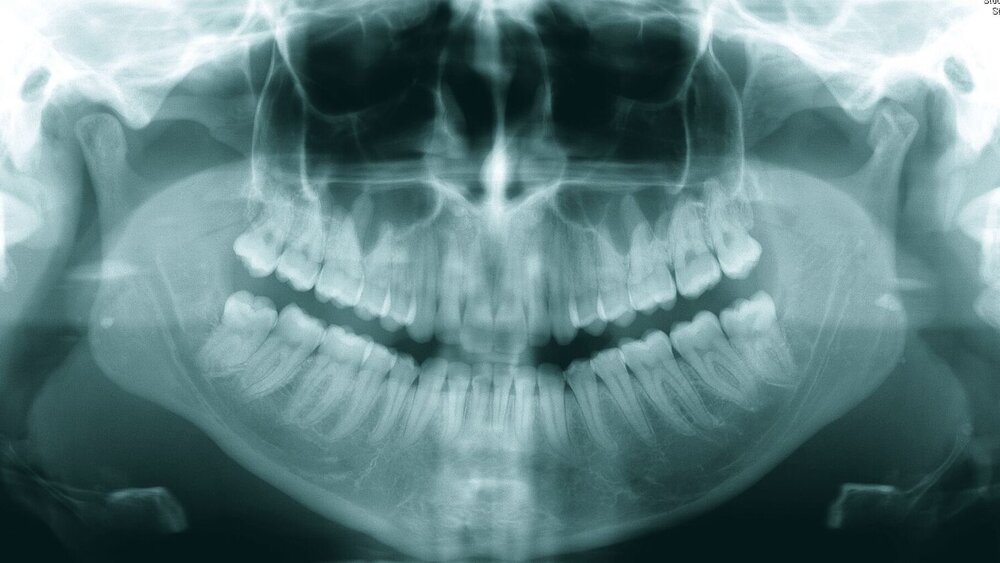

Eine 20-jährige Patientin wurde durch ihren Hauszahnarzt an unsere Poliklinik zur Entfernung aller Weisheitszähne überwiesen (Abbildung 1). Der Hauszahnarzt habe vergeblich versucht, diese zu extrahieren, die Lokalanästhesie habe keine ausreichende Wirkung erzielt.

Die Entfernung aller Weisheitszähne wurde schließlich nach einem weiteren frustranen Extraktionsversuch unter Lokalanästhesie in Intubationsnarkose durchgeführt, der postoperative Verlauf gestaltete sich komplikationslos, auffällige Blutungen traten nicht auf (Abbildungen 2 und 3).